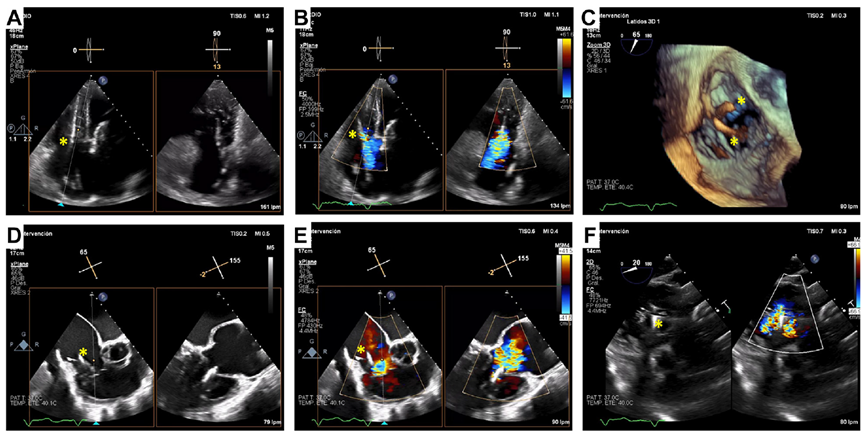

基線經胸和經食道超聲

術后經食道超聲,僅微量瓣周漏